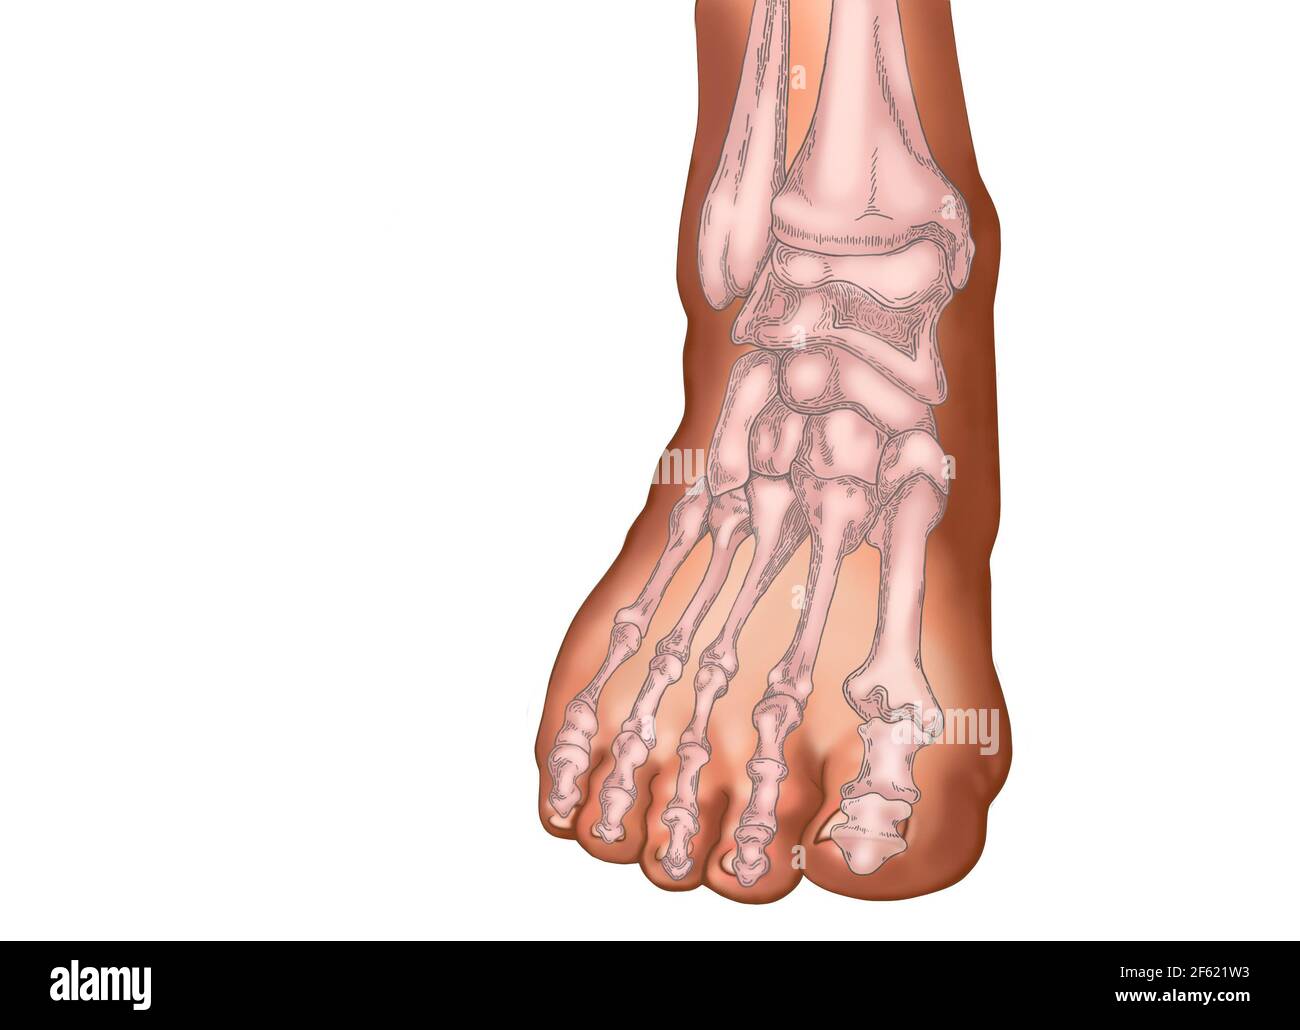

RF2WNN754–Illustration médicale des principales parties des os du pied en vue antérieure, avec annotations.